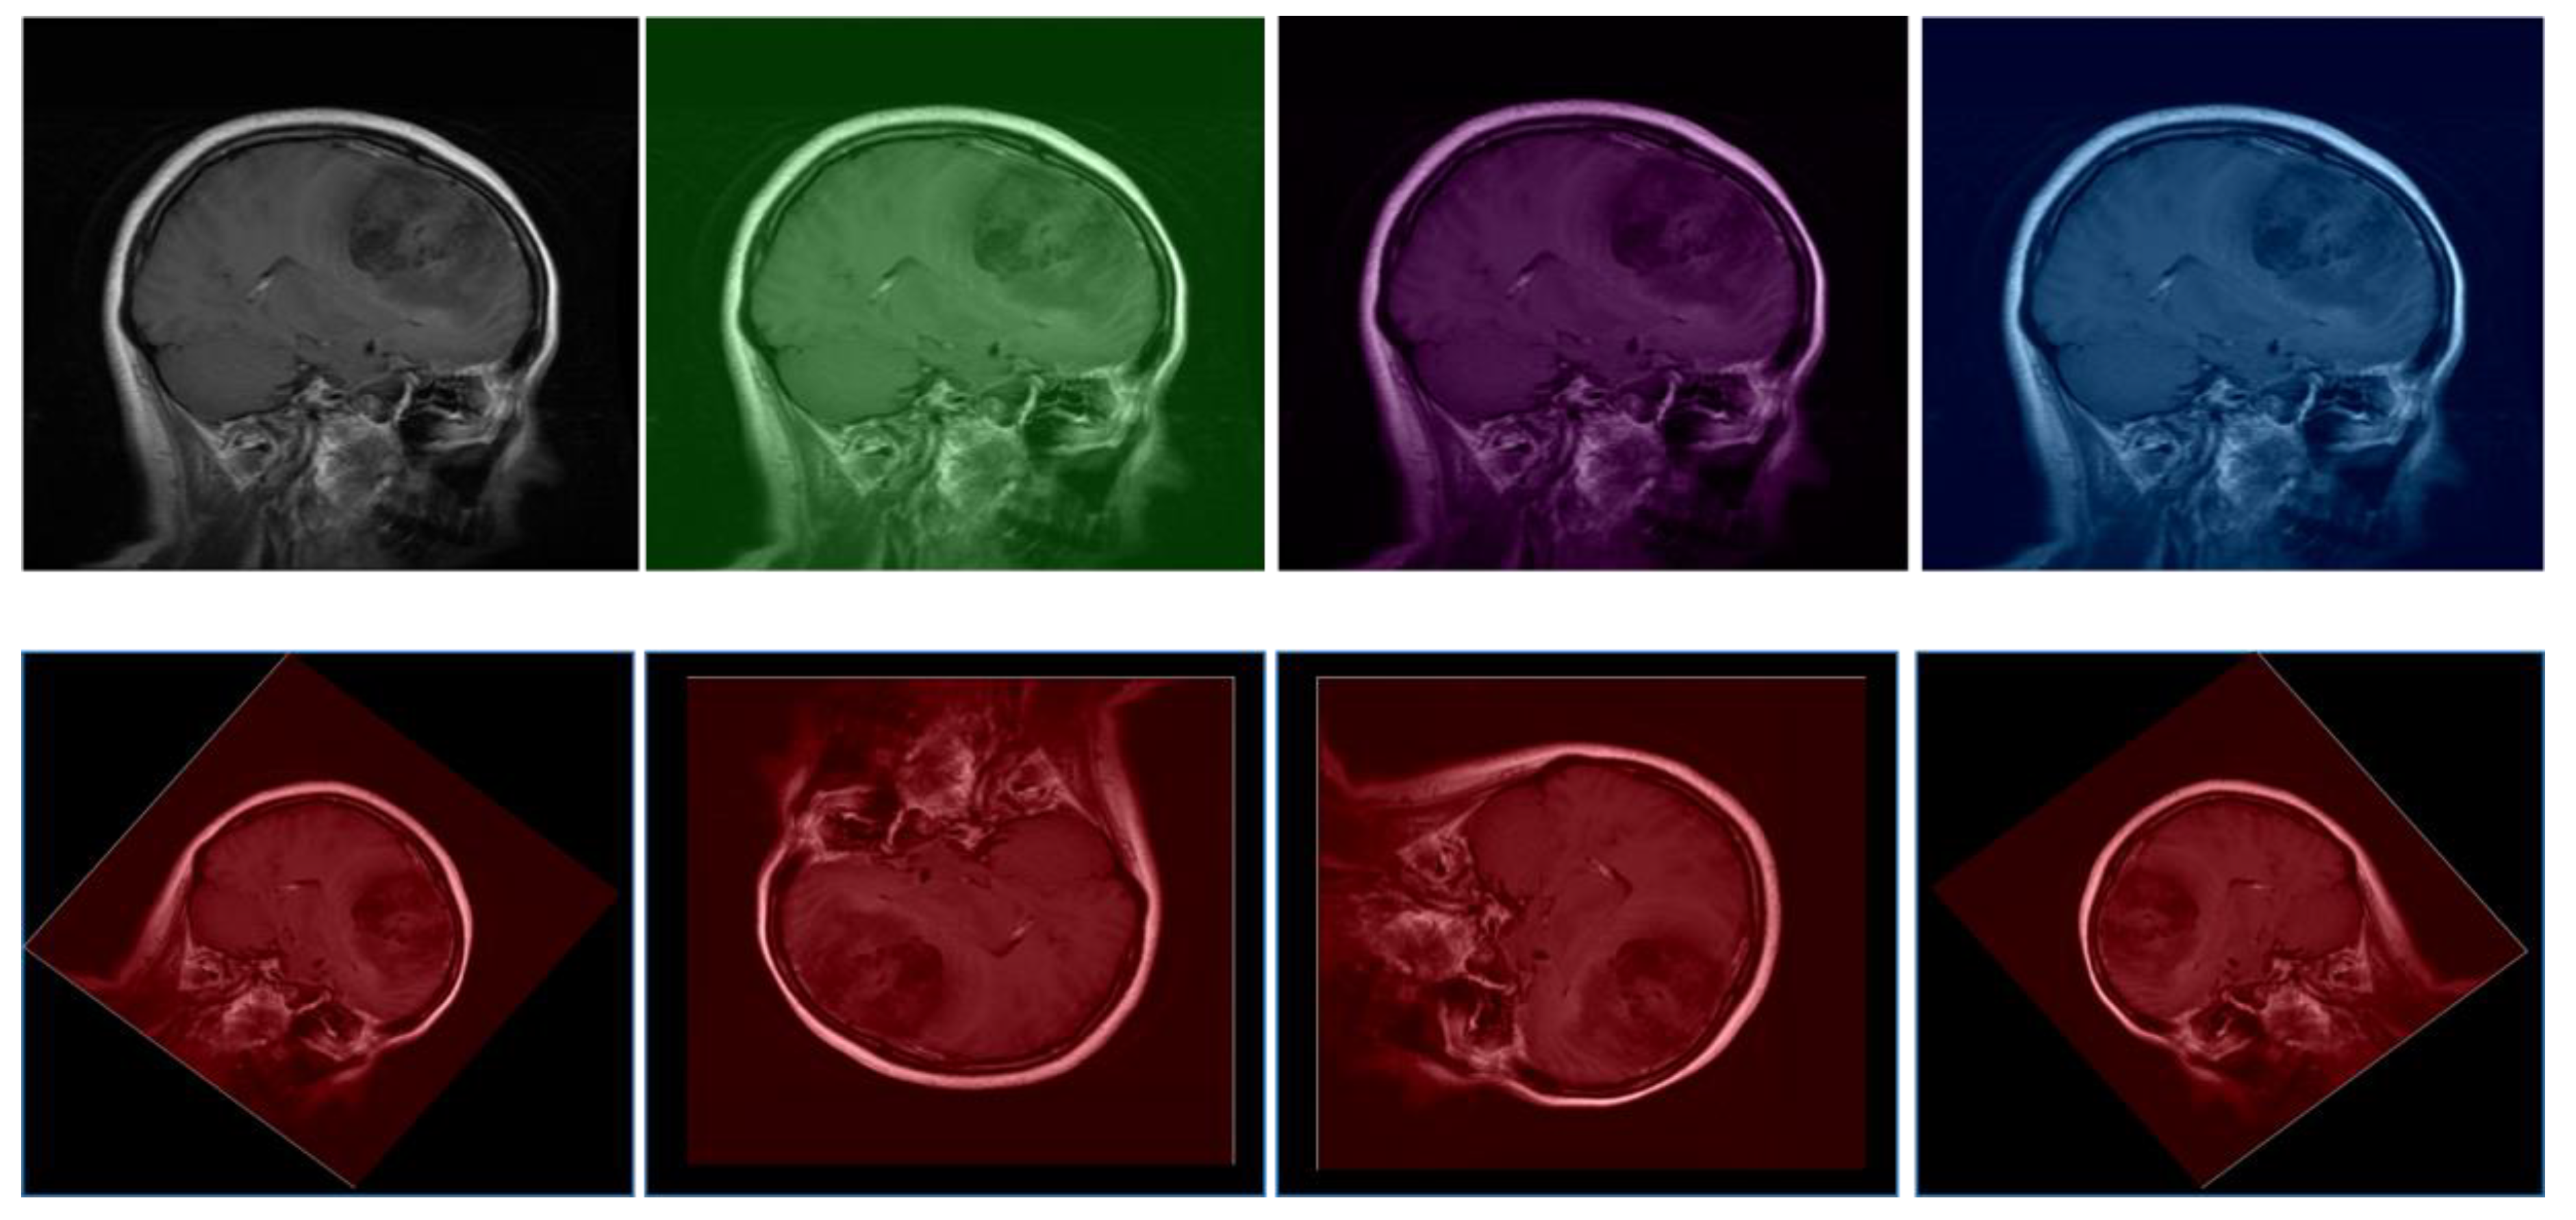

4.2. Data Preprocessing

| Preprocessing Steps | Skull stripping, image normalization, resampling, augmentation |

| Image Normalization | Ensures uniform intensity scales across different imaging modalities. MRI scans undergo Z-score normalization, adjusting pixel values to have a mean of zero and a standard deviation of one. CT scans use windowing to highlight intensity ranges relevant to hemorrhages. |

| Resampling | Standardizes resolution across all images to ensure consistent voxel sizes. This step enables the model to learn scale-invariant features and prevents variations in voxel dimensions from affecting training. |

| Skull Stripping | Removes non-brain tissues, particularly in MRI scans, to focus the model’s attention on brain structures where tumors are located. Automated algorithms leveraging anatomical atlases or deep learning methods are used for precision. |

| Augmentation | Enhances model robustness and prevents overfitting by applying rotation, flipping, and slight translations. These transformations help the model generalize better to variations present in clinical settings. |